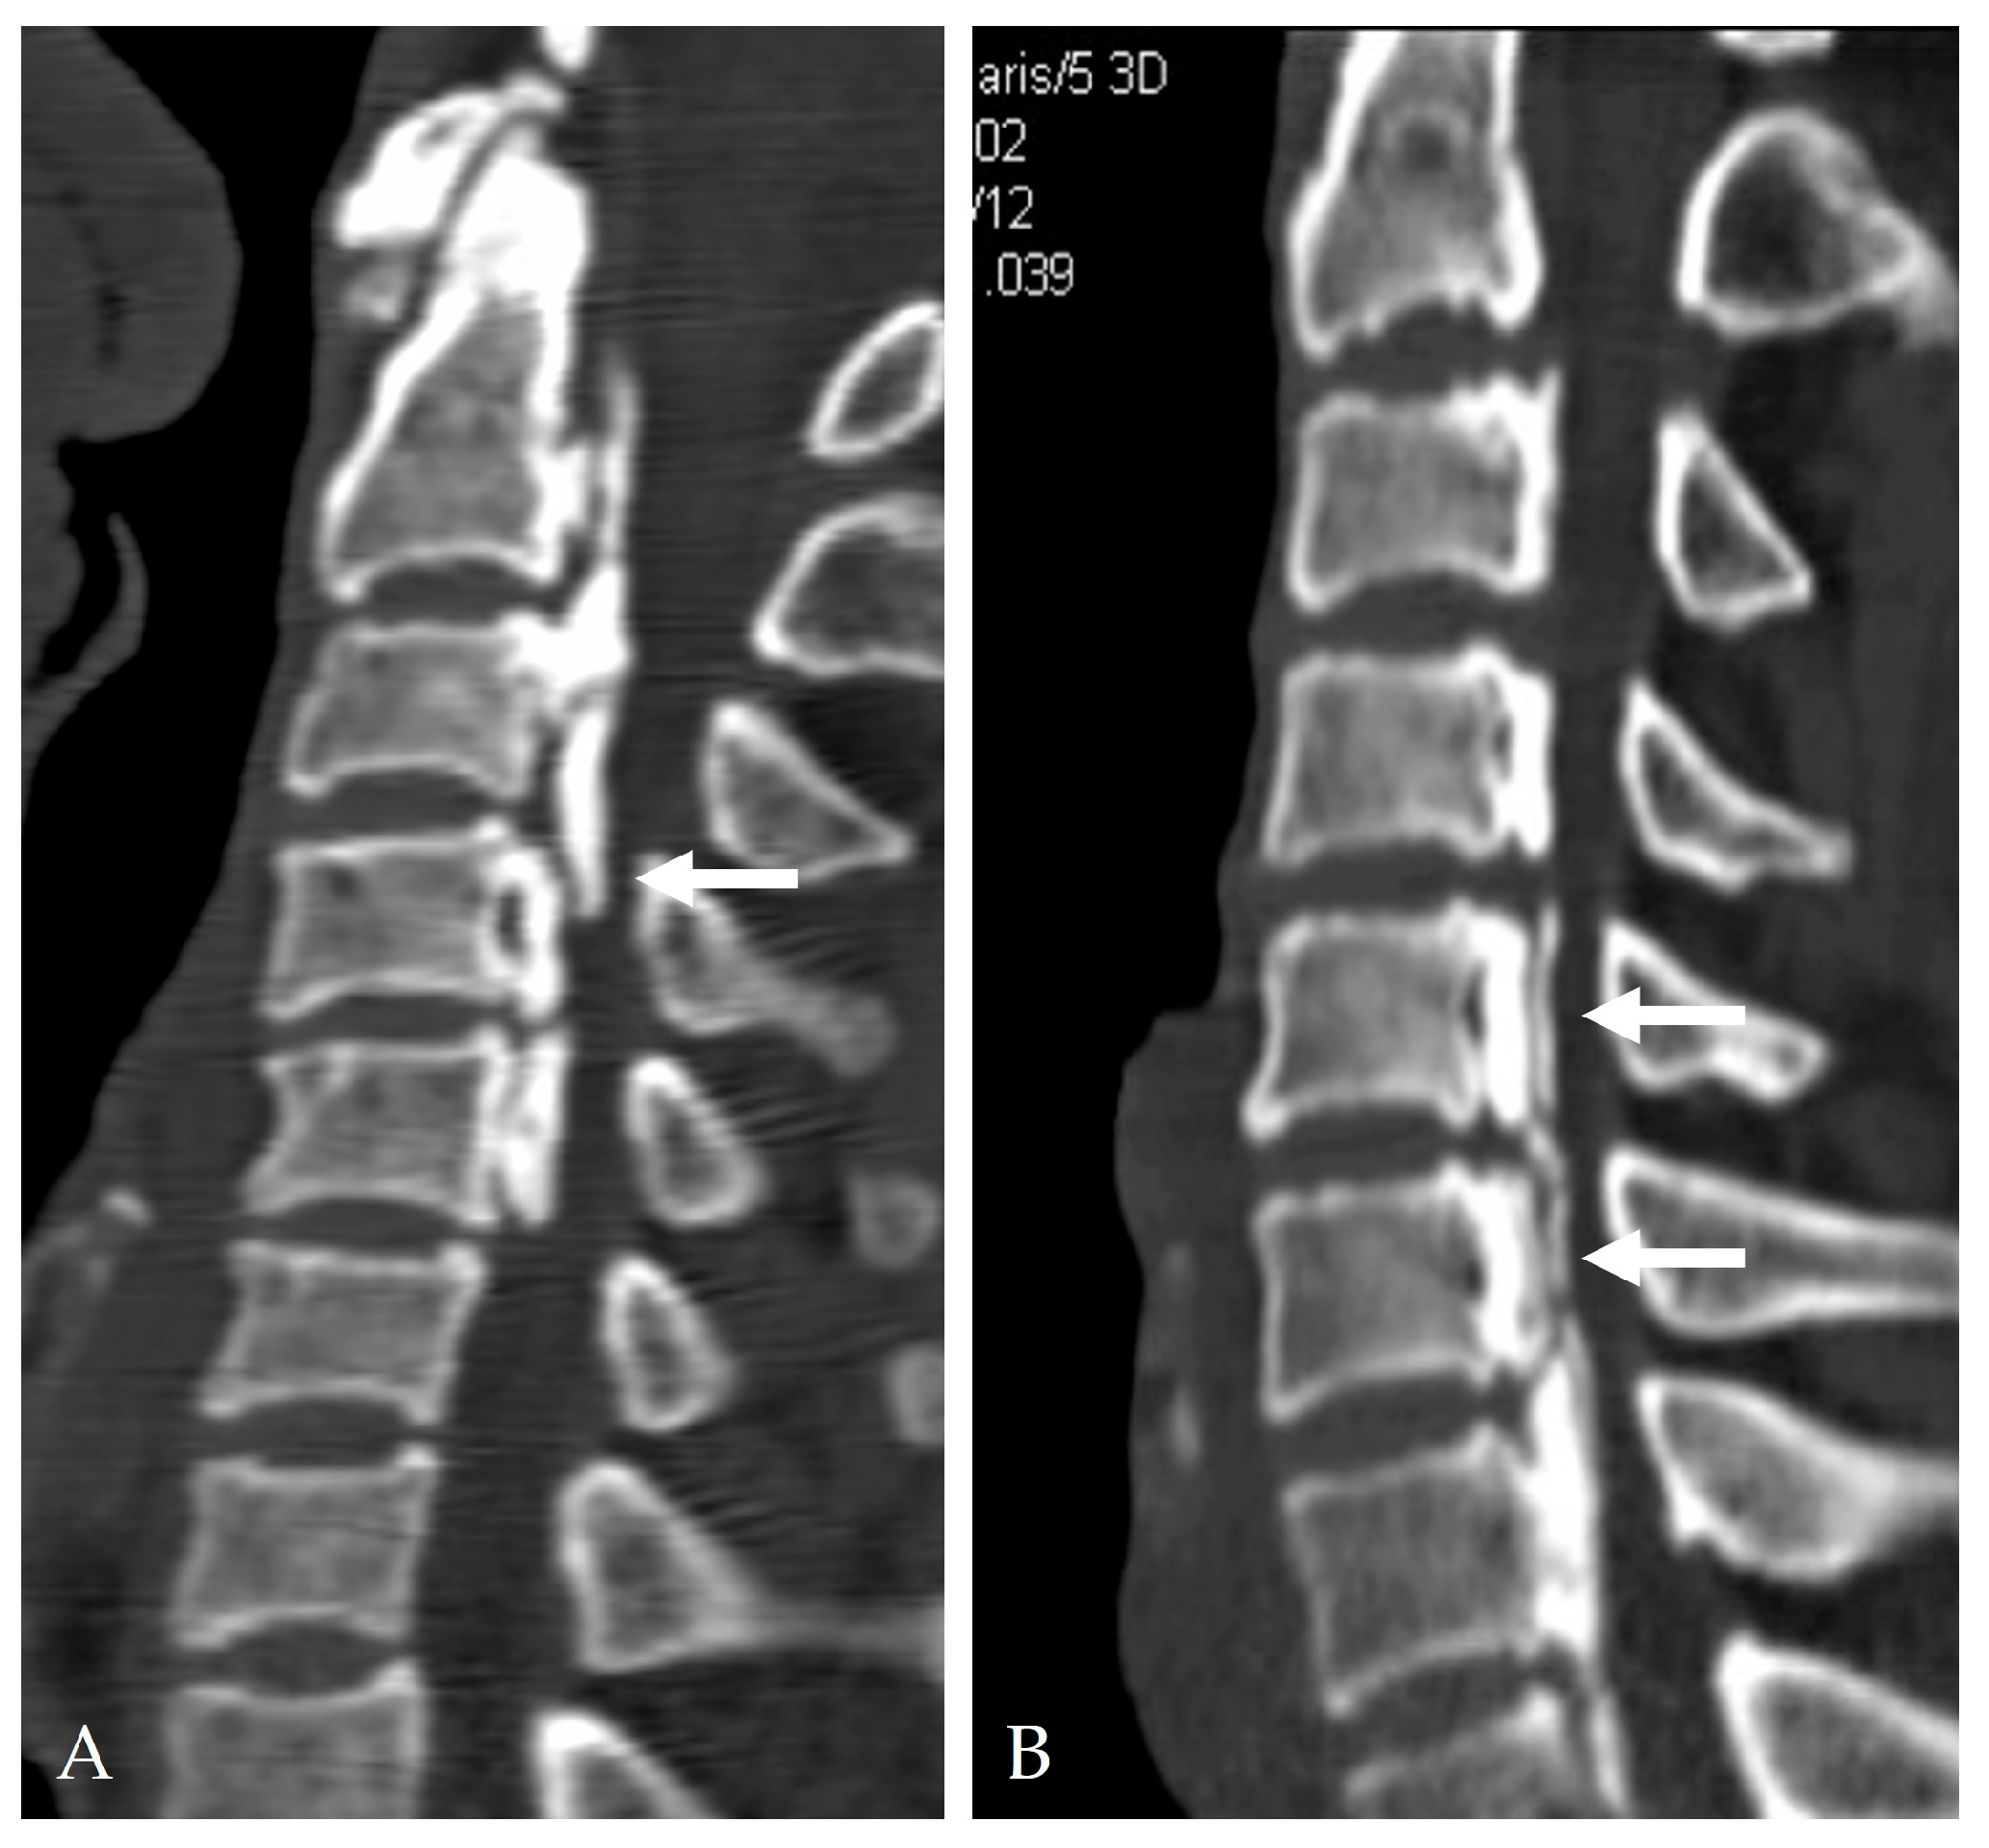

2.4. Radiologic Predictors and Morphological Correlates

- Broad-based or continuous/mixed-type OPLL: Confers approximately 10-fold higher risk of DT than segmental types [37].

- Min, J.H.; Jang, J.S.; Lee, S.H. Clinical significance of the double-layer sign on computed tomography in OPLL. Neurosurgery 2007, 61, 118–121. [Google Scholar] [CrossRef]

- Yang, H.; Yang, L.; Chen, D.; Wang, X.; Lu, X.; Yuan, W. Implications of different patterns of the “double-layer sign” in cervical OPLL. Eur. Spine J. 2015, 24, 1631–1639. [Google Scholar] [CrossRef]

- Epstein, N.E. Identification of OPLL extending through the dura on preoperative CT of the cervical spine. Spine 2002, 27, 182–186. [Google Scholar]

- Mizuno, J. Radiologic evaluation of ossification of the posterior longitudinal ligament with dural ossification. Neurosurg. Clin. N. Am. 2018, 29, 55–61. [Google Scholar] [CrossRef] [PubMed]